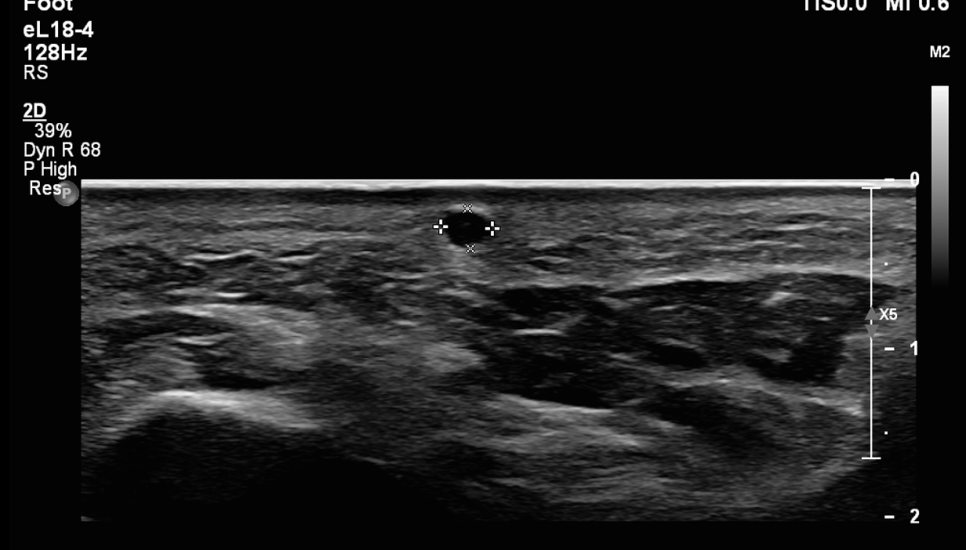

환자분의 초음파 사진입니다.

작은 원 모양의 혹이 관찰됩니다. 크기는 약 0.5cm 정도입니다.

가로, 세로 비슷한 크기입니다. 혈관이 지나가거나 신경이 지나가는 것도 없습니다. 대부분의 발바닥의 혹은 섬유종이라고 합니다. 크기가 좀 더 크고 통증이 없습니다. 그냥 굳은살과 비슷한 느낌이라고 보시면 됩니다.

하지만 이것은 다른 것입니다. 그럼 뭐냐?

표피낭종 입니다.